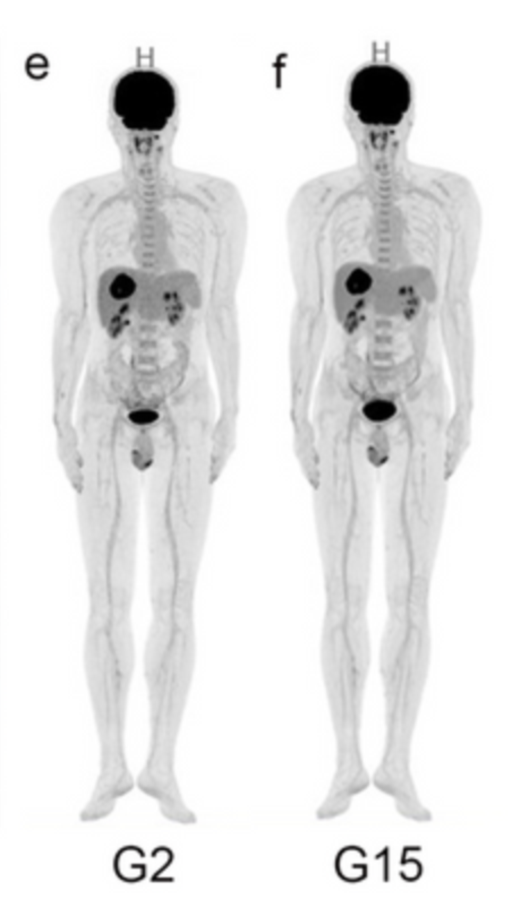

圖2肝內膽管癌(ICC)受試者G2和G15的全身PET三維MIP圖像對比

研究方法:研究納入了156名肝臟腫瘤患者,其中78名患者接受了uEXPLORER全身PET/CT檢查,采集時間為15分鐘,而后分別重建為2分鐘(G2組)和15分鐘(G15組)兩組圖像數據。作為對照組,另外78名患者接受了傳統PET/CT——uMI 780 PET/CT的檢查(G780組)。在定量指標評估方面,本文測算了每位患者最大腫瘤病灶的SUVmax、正常肝臟組織SUVmean和腫瘤-肝臟本底比值(腫瘤SUVmax與肝臟正常組織SUVmean的比值,TLR)。在病變可探查性分析中,以G15組作為參考,評估2分鐘采集時間的數據(G2組)在視覺評估方面以及病灶SUVmax、TLR等半定量參數方面的診斷性能;對G2組數據的肝臟病灶SUVmax和TLR進行了接受者操作特性曲線(ROC曲線分析);同時,所有這些患者手術標本的病理結果作會為對比的診斷金標準。

研究結果:對于所有患者,G2能夠顯示出G15中發現的病灶。G2中遺漏3個在G15組中顯示出的具有較低18F-FDG代謝的淋巴結,不過在最終的TNM分期方面,G2、G15和G780之間都沒有明顯差異。在異常代謝中,無論是良性病變還是惡性病變,G2和G15的肝臟SUVmean都高于G780(P<0.05);G2的腫瘤SUVmax和TLR都與G15和G780的相當。ROC曲線分析(SUV截斷點:4.34,TLR截斷點:1.34)表明,G2在檢測肝癌方面也有良好的敏感性。

研究結果表明,對于肝癌患者,由于全身PET/CT超長的軸距和超高的靈敏度,在2分鐘短時間采集條件下(G2組)的診斷性能與采集15分鐘的圖像相當,與傳統PET/CT全身檢查也有相似的診斷效能。過去通過傳統PET/CT,一次全身腫瘤檢查通常需要15~20分鐘的采集時間,如今借助全身PET/CT uEXPLORER這樣新技術有望直接縮短至2分鐘,更短的檢查時間能使科室診斷流程更加流暢,大幅提升患者的就診體驗。更重要的是,對于癲癇患者、難以耐受劇痛的腫瘤患者等人群而言,過去由于難以長時間保持靜止不動,無法正常進行PET/CT檢查,如今借助全身PET/CT進行短時間快速采集,讓這部分患者也能從中受益。